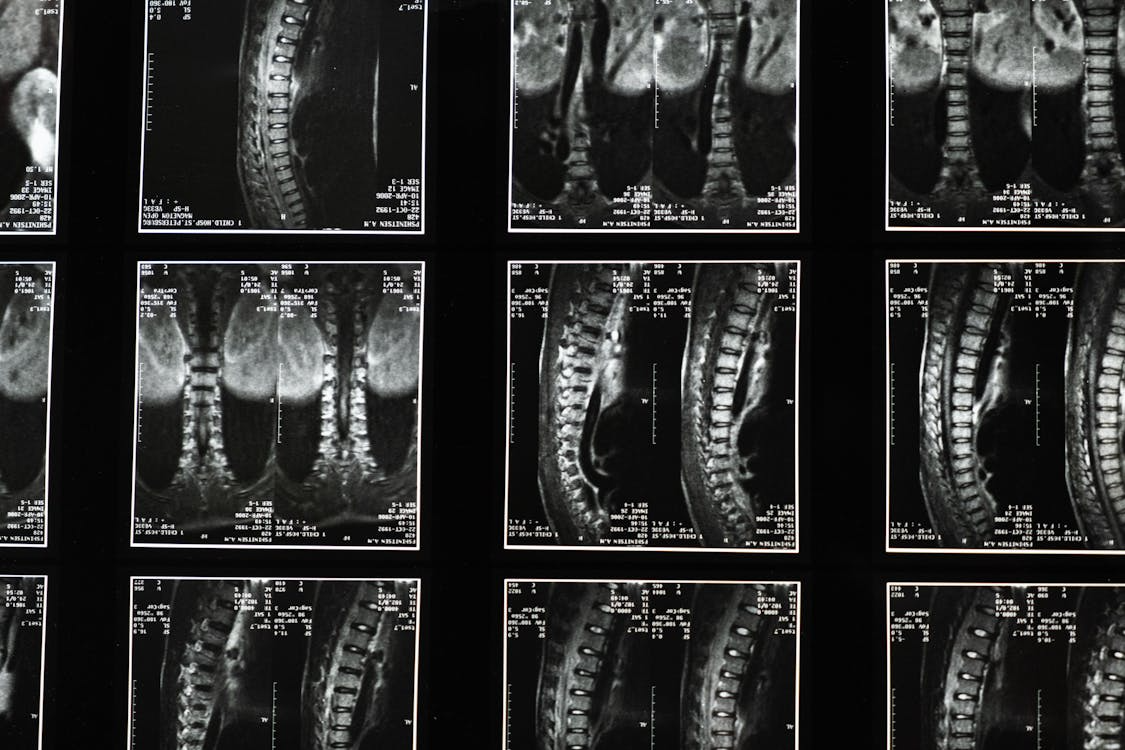

Spondylolisthesis is a common spinal condition that involves one or more of the vertebrae in the spine slipping forward and coming into contact with the nerves or adjacent bones/ ligaments. This can result in intermittent or persistent pain that can range in severity. However, symptoms are not just limited to pain and may include:

When one vertebra slips forward over the one below it, your spine loses its normal alignment, creating instability in that section of your back, which means the surrounding muscles have to work much harder to keep you upright and stable. These muscles often become tight and painful from the extra effort.

The slip changes how forces travel through your spine when you move. Normally, weight and pressure are distributed evenly, but with spondylolisthesis, some areas take on more stress than they should. This can lead to pain and further wear and tear over time.

Spondylolisthesis can significantly affect your nerves, particularly when the slipped vertebra narrows the spaces where nerves pass through your spine. It can squeeze the spinal canal – the main tunnel that houses your spinal cord. This compression can put pressure directly on the spinal cord itself, causing problems with nerve signals travelling between your brain and the rest of your body.

More commonly, the condition affects individual nerve roots that branch off from the spinal cord. These nerves exit through small openings called foramina, and when a vertebra slips, these openings can become narrower. The compressed nerves struggle to function properly, leading to various symptoms.